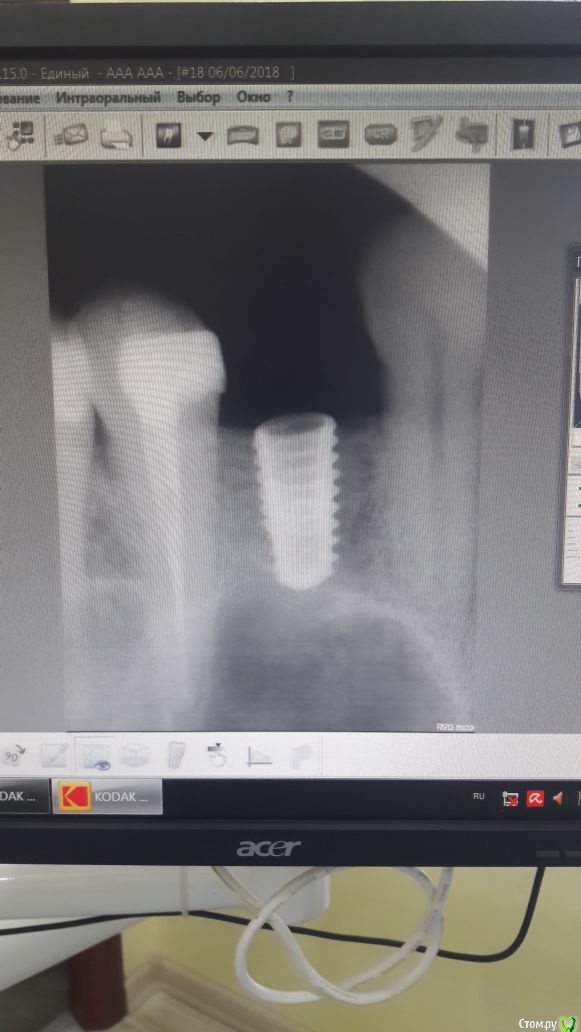

Игорь Надель Опубликовано 13 июля, 2018 Поделиться Опубликовано 13 июля, 2018 Установка импланта AnyOne 4.0 х 8мм, 2 сегмент зуб 24 места по горизонтали и по вертикали достаточно, сверление по протоколу, кортикальное сверло не использовал. Первичную стабилизацию получил, ушил нить 5/0 через шесть дней на приеме увидел что шов дистальный разошелся. контрольный снимок никакой явной патологии и проблемы не показал. Через месяц 2 снимок обратилась с жалобами на гнойничок над имплантом, вскрыл промыл установил формирователь. Ваше мнение выкрутить или оставить. если оставить то дальнейшие действия Ссылка на комментарий

Игорь Надель Опубликовано 13 июля, 2018 Автор Поделиться Опубликовано 13 июля, 2018 имплантат недозаглублен. Выкручивайте и ставьте нормально. Места кстати по высоте было изначально недостаточно, вы сделали замеры, увидели 8мм кости и закрутили, но это неправильно.Имплант установлен вровень с костью, это был предпоследний снимок, потом было проведено докручивание. По КТ место было 7,79, поэтому был выбран имплантат 8 мм и закручен бикортикально. Что было не верно 1 Ссылка на комментарий

Sampson Опубликовано 13 июля, 2018 Поделиться Опубликовано 13 июля, 2018 (изменено) Имплант установлен вровень с костью, это был предпоследний снимок, потом было проведено докручивание. По КТ место было 7,79, поэтому был выбран имплантат 8 мм и закручен бикортикально. Что было не верно ну а зачем тогда вводить нас в заблуждение . подписали бы что снимок до подкручивания.на снимке от 6.07 назовём его !!!!с Заглушкой!!! Викручивай. Изменено 13 июля, 2018 пользователем Sampson Ссылка на комментарий